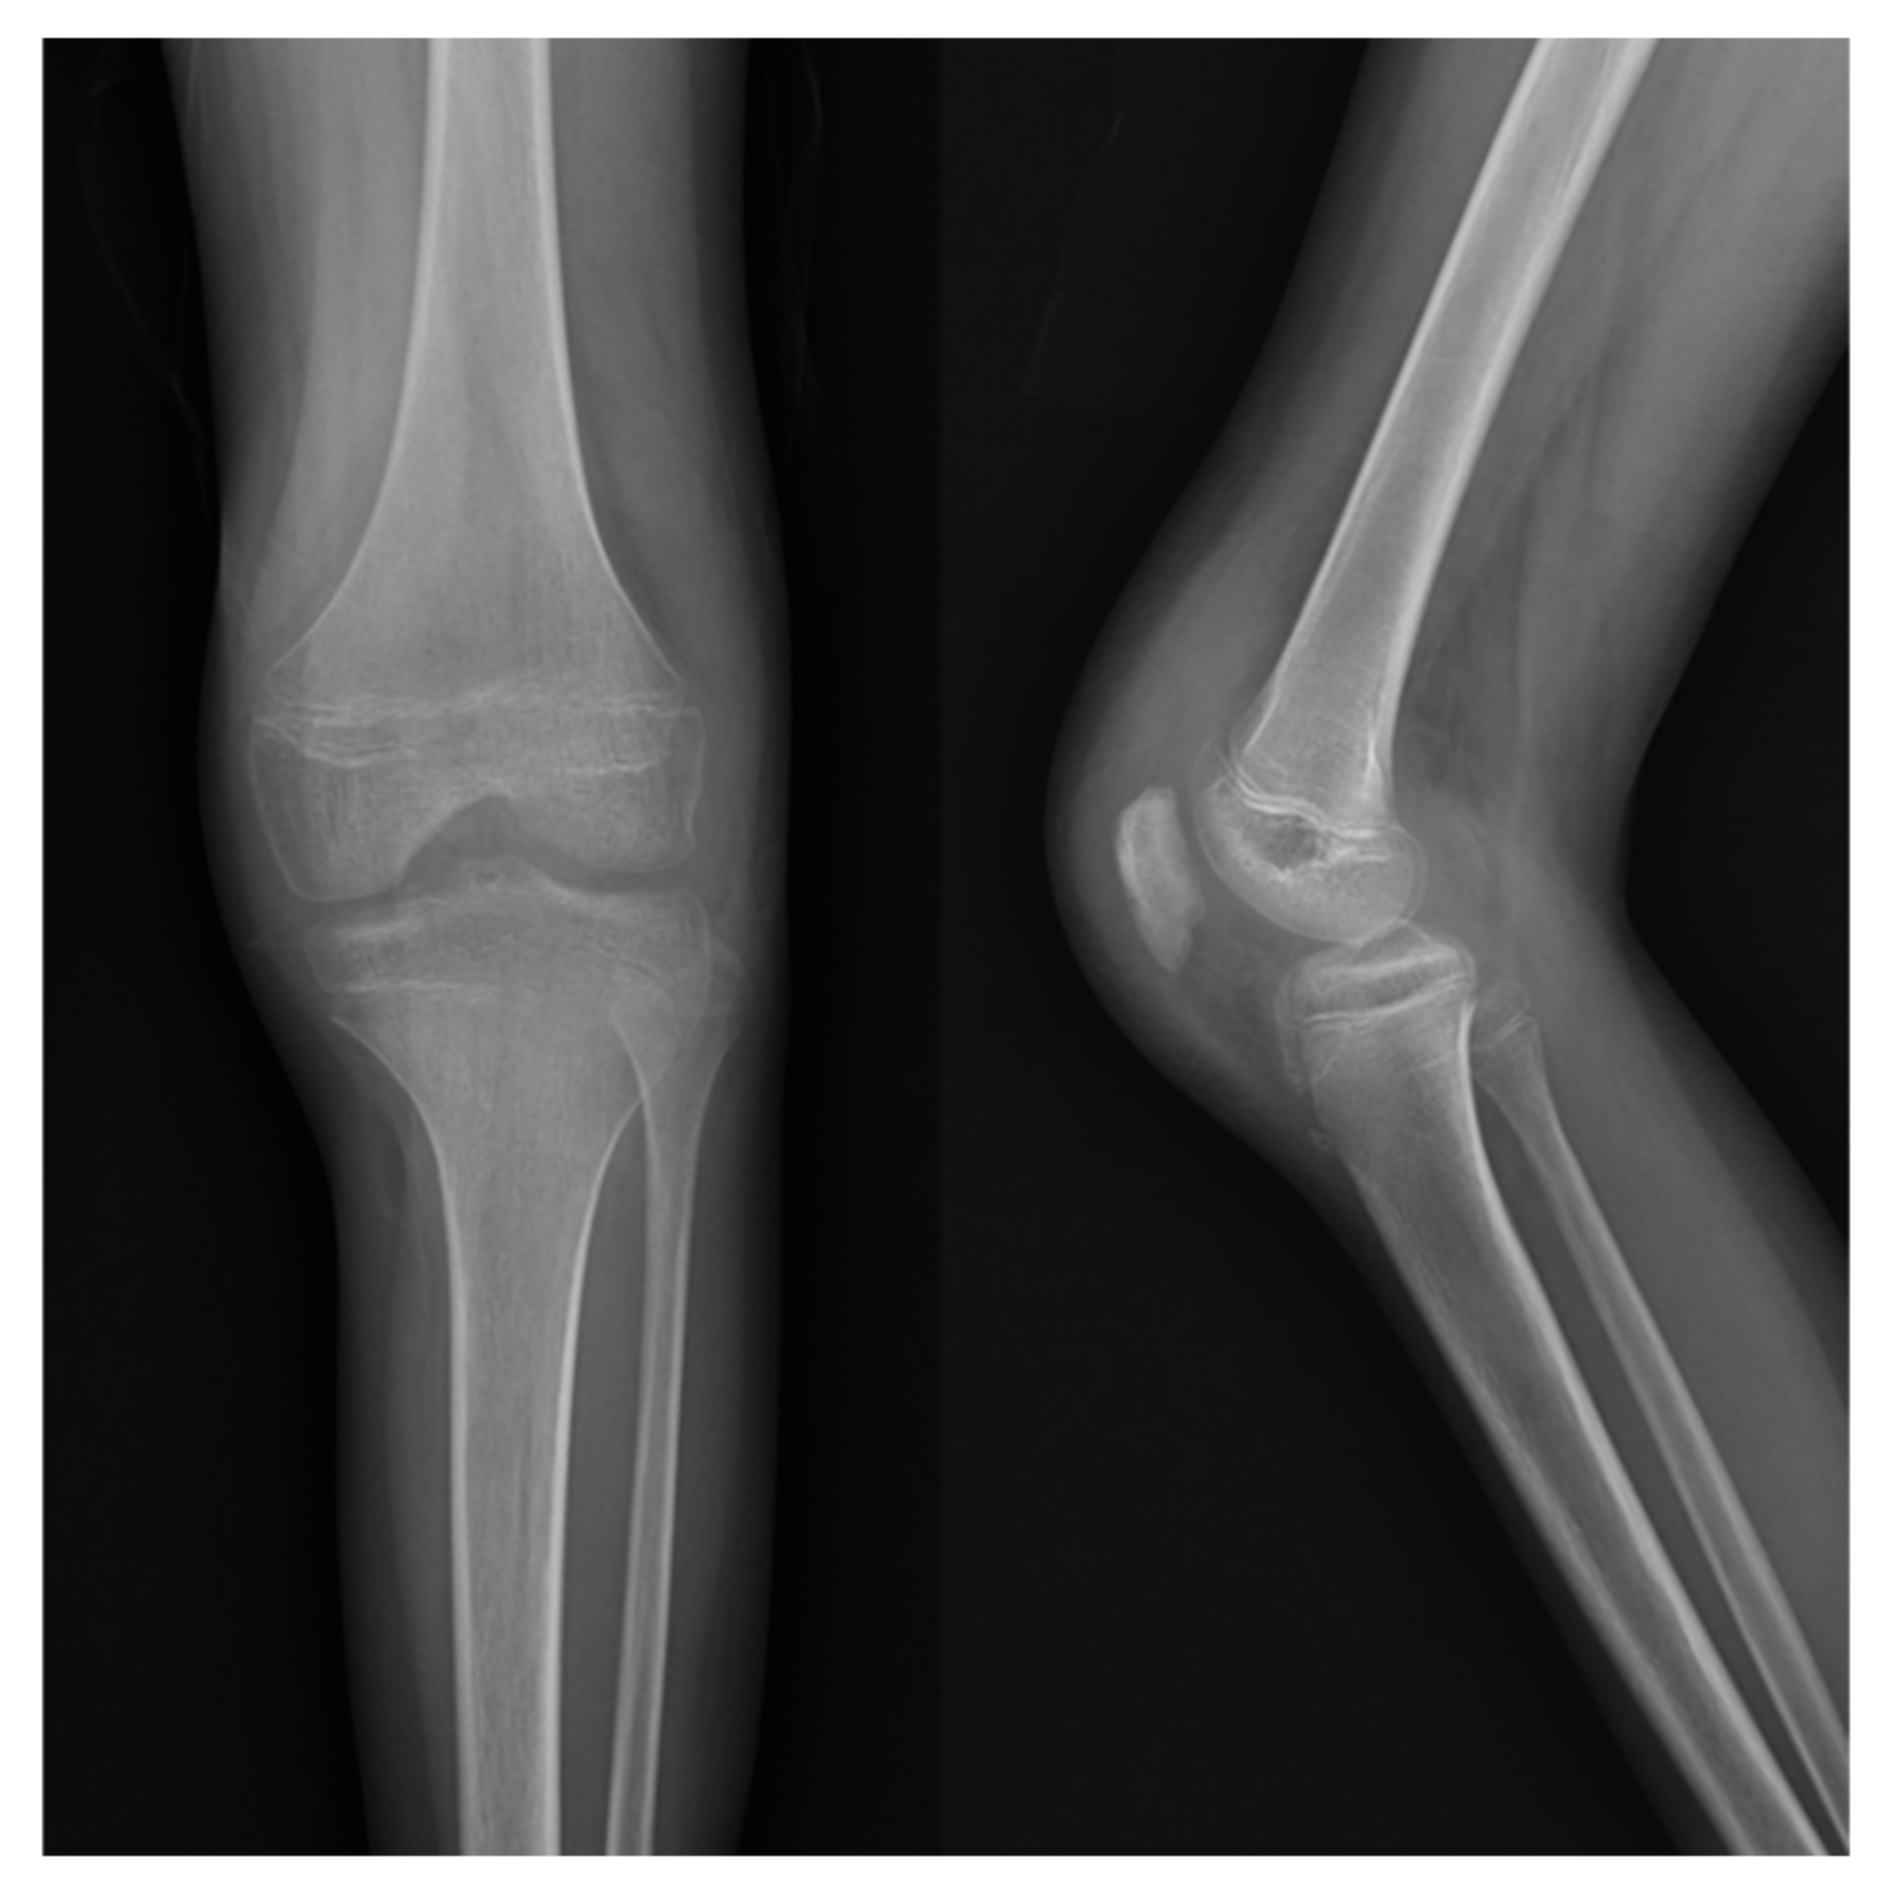

Patellar Osteomyelitis in a 9-Year-Old Patient with Chronic Granulomatous Disease: A Case Report

2. Case Report